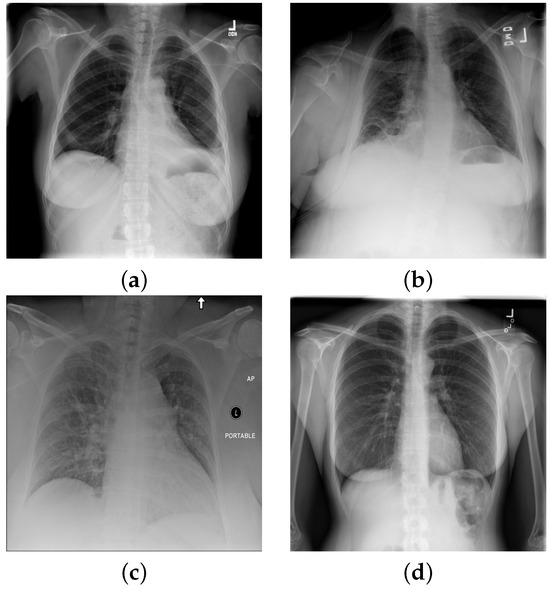

Atelectasis is the absence of inflation (i.e., collapse) of part of the lung, resulting in reduced volume and increased opacity of the lung tissue on radiographs [46], see on Figure 2a). Cardiomegaly is the enlargement of the heart, whereby the transverse diameter of the cardiac silhouette is greater than or equal to 50% of the transverse diameter of the chest [47] (see Figure 2b,c). Consolation refers to the increased lung opacity on radiographs with various patterns, indicating that the lung tissue is filled with liquid, such as exudate, pus, water, or blood, instead of air [48] (see Figure 2b). Although pneumonia is the most common cause of consolidation, it is not the sole causative factor. Edema is another opacity of the lungs that may appear as ill-defined nodular opacities tending to confluence in alveolar edemas or present as peripheral lines in interstitial edema (see Figure 2c). In the pneumothorax, the radiograph shows a thin, sharply defined opaque (white) line (displaced visceral pleura) outlined by a lucent (dark) air-filled lung [49]. For a special case with no findings see Figure 2d.

Figure 2. Chest X-ray images with with distinct conditions: (a) atelectasis; (b) cardiomegaly; (c) cardiomegaly, consolidation, edema; (d) no finding.